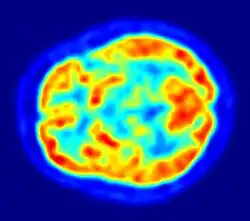

PET imaging with oxygen-15 indirectly measures blood flow to the brain. In this method, increased radioactivity signal indicates increased blood flow which is assumed to correlate with increased brain activity. Because of its two-minute half-life, oxygen-15 must be piped directly from a medical cyclotron for such uses, which is difficult.[17]

PET imaging with FDG takes advantage of the fact that the brain is normally a rapid user of glucose. Standard FDG PET of the brain measures regional glucose use and can be used in neuropathological diagnosis.

Brain pathologies such as Alzheimer's disease greatly decrease brain metabolism of both glucose and oxygen in tandem. Therefore FDG PET of the brain may also be used to successfully differentiate Alzheimer's disease from other dementing processes, and also to make early diagnoses of Alzheimer's disease. The advantage of FDG PET for these uses is its much wider availability. In addition, some other fluorine-18 based radioactive tracers can be used to detect amyloid-beta plaques, a potential biomarker for Alzheimer's in the brain. These include florbetapir, flutemetamol, Pittsburgh compound B (PiB) and florbetaben.[18]

PET imaging with FDG can also be used for localization of "seizure focus". A seizure focus will appear as hypometabolic during an interictal scan.[19] Several radiotracers (i.e. radioligands) have been developed for PET that are ligands for specific neuroreceptor subtypes such as [11C]raclopride, [18F]fallypride and [18F]desmethoxyfallypride for dopamine D2/D3 receptors; [11C]McN5652 and [11C]DASB for serotonin transporters; [18F]mefway for serotonin 5HT1A receptors; and [18F]nifene for nicotinic acetylcholine receptors or enzyme substrates (e.g. 6-FDOPA for the AADC enzyme). These agents permit the visualization of neuroreceptor pools in the context of a plurality of neuropsychiatric and neurologic illnesses.